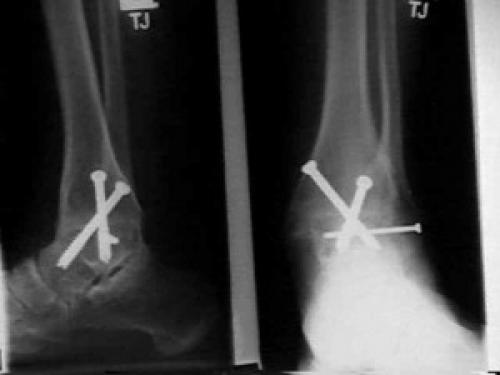

Артодез на этом суставе могут проводить как под общей, так и под спинальной анестезией. Для сращивания могут использовать специальные шурупы, винты, пластины, стержни, костные трансплантаты и другие медицинские приспособления для фиксации.

Также при выполнении артродеза к двум костям могут прикрепляться металлические импланты (винты, стержни, пластины на шурупах и др.). Это делается для того, чтобы удерживать кости в неподвижном положении, благоприятствующем росту новой кости.

В некоторых случаях применяются аппараты внешней фиксации. Классическим считается аппарат Илизарова, или компрессионно-дистракционный аппарат, который с момента изобретения сильно модифицировался. Потому сейчас отзывы пациентов о дискомфорте при его ношении плавно сходят на нет.

Для облегчения костного сращения широко используется комбинация вышеуказанных методов.